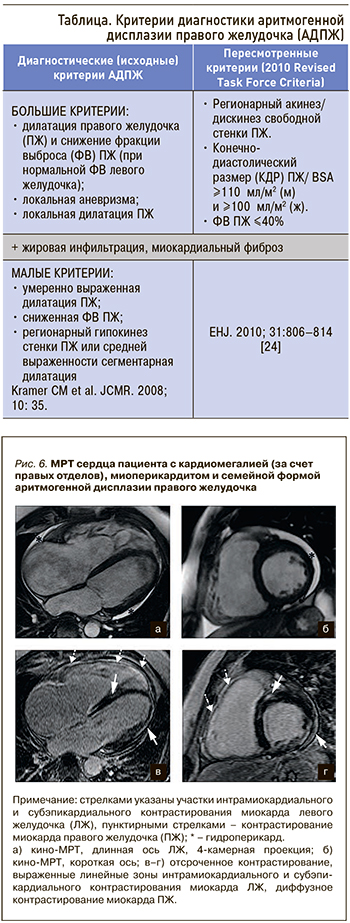

В 2010 г. были пересмотрены критерии диагностики АДПЖ (Task Force Criteria, 2010), основное значение сейчас уделяется количественным характеристикам – индексированному (нормализованному по площади поверхности тела) объему правого желудочка и фракции выброса ПЖ, изменение которых при наличии участка акинеза или дискинеза свободной стенки ПЖ достаточно для подтверждения диагноза АДПЖ [24]. Применение пересмотренных критериев (табл.) позволило повысить их специфичность в диагностике АДПЖ.

Феномен отсроченного контрастирования миокарда встречается и у пациентов с аритмогенной правожелудочковой КМП. МРТ с гадолинием выявляет участки миокардиального фиброза в стенках левого и правого желудочков (рис. 6).